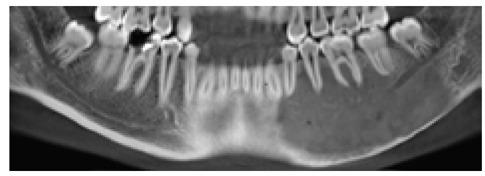

颌骨纤维结构不良:系列病例回顾性研究及文献复习

Jawbone fibrous dysplasia: retrospective evaluation in a cases series surgically treated and short review of the literature.

Fibrous dysplasia is a fibro-osseous osteopathy in which the normal bone architecture is replaced by fibrous tissue and non-functional trabeculae-like osseous structures. In head and neck area monostotic or polyostotic lesions cause a progressively expanding destructive bone swelling producing cosmetic deformities and functional impairments. The aim of this article is to present a retrospective review of a clinical case series with pathologically confirmed jawbone fibrous dysplasia for over an 8-year-period.

Clinical presentation and radiographic features of fibrous dysplasia affecting the jawbone skeletal area, surgical procedures performed including the reconstructive methods employed and clinical outcomes were analysed for each patient.

Seven cases were classified as having monostotic fibrous dysplasia while the others four cases were classified as having polyostotic form. The mandible was most commonly involved. The most common presenting features included marked facial deformity, intraoral bulging, malocclusion and dental alterations. Aesthetic and/or functional impairments were the major indications for surgical treatment in all the patients of this series. Six patients underwent bone remodelling while in the remaining cases subtotal or total resection was performed. Bone reconstruction by means of autologous free bone grafts or revascularized free bone flaps was made in three cases.

The choice of the tailored therapeutic approach should be evaluated according the patient's age, rate of growth, anatomic location, type of involvement and the presence or not of functional disturbances and cosmetic alterations. Surgery remains the best therapeutic option.

纤维结构不良是一种纤维骨性骨病,其中正常骨结构被纤维组织和非功能性小梁样骨结构所取代。在头颈部,单发性或多发性病变导致进行性扩展的破坏性骨肿胀,导致美容畸形和功能障碍。本文的目的是回顾性分析一组经过 8 年以上病理证实的颌骨纤维结构不良的临床病例系列。

分析了影响颌骨骨骼区域的纤维结构不良的临床表现和影像学特征、手术程序,包括所采用的重建方法和临床结果。

7 例被分类为单发性纤维结构不良,而另外 4 例被分类为多发性纤维结构不良。下颌骨最常受累。最常见的表现包括明显的面部畸形、口腔内膨出、咬合不正和牙齿改变。在本系列的所有患者中,美容和/或功能障碍是手术治疗的主要指征。6 例患者接受了骨重塑,而在其余病例中进行了次全或全切除术。在 3 例病例中,通过自体游离骨移植或带血管游离骨瓣进行骨重建。

应根据患者的年龄、生长速度、解剖位置、受累类型以及是否存在功能障碍和美容改变来评估定制治疗方法的选择。手术仍然是最佳治疗选择。